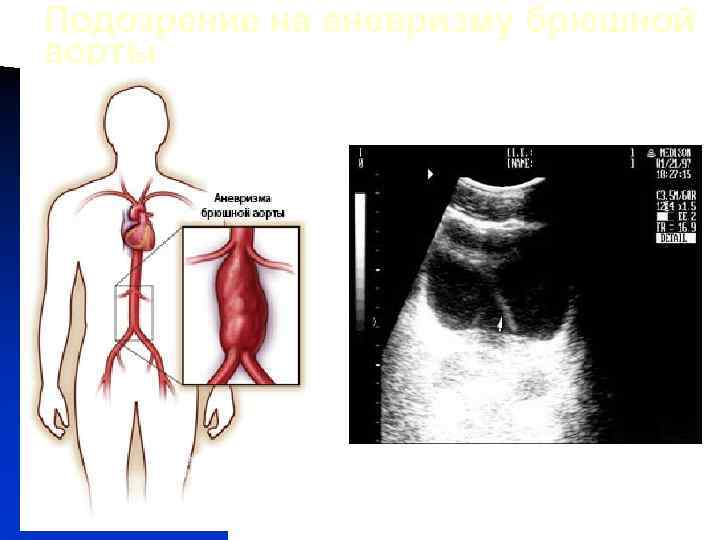

Подозрение на аневризму брюшной аорты УЗИ Аневризма Требуется уточнение РКТ с усилением или МРА Аортография (по показаниям)

Подозрение на аневризму брюшной аорты